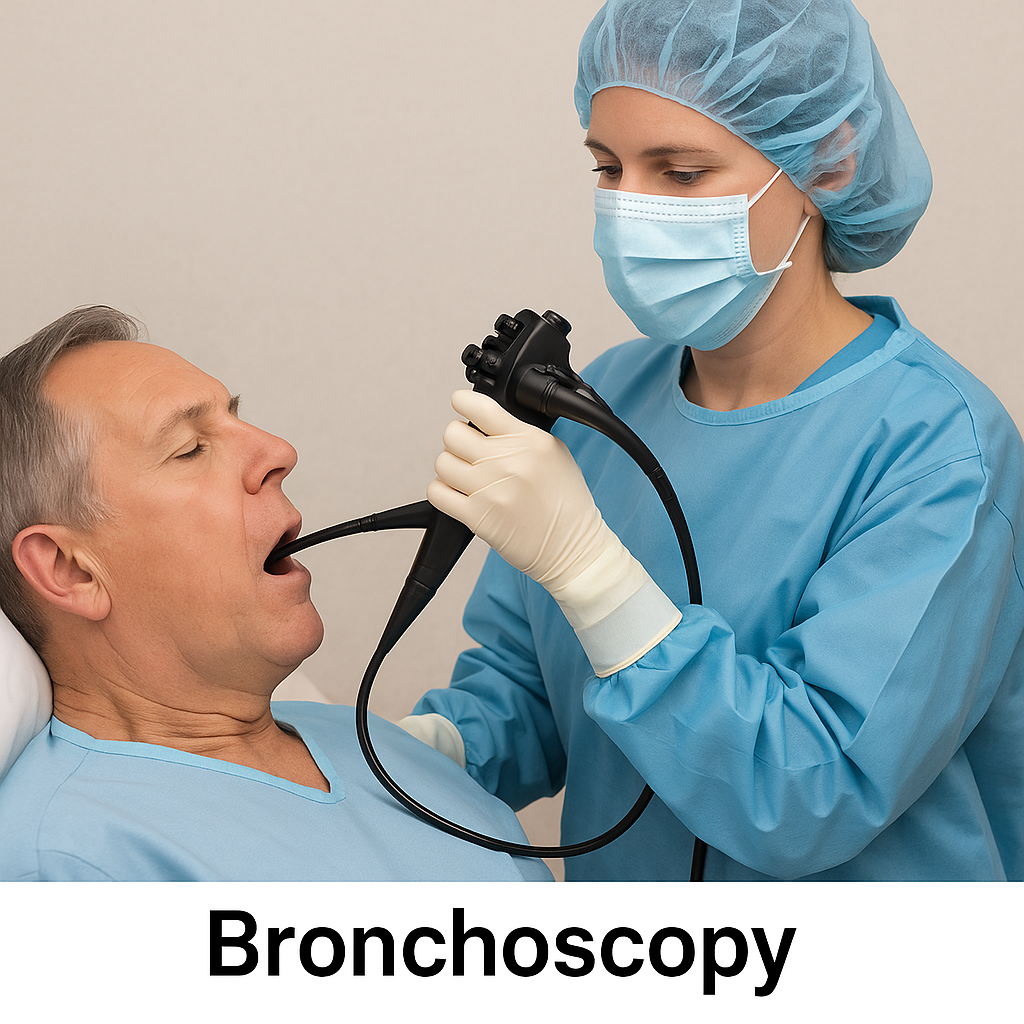

Bronchoscopy (બ્રોન્કોસ્કોપી):

- બ્રોન્કોસ્કોપીમાં બ્રોન્કોસ્કોપની મદદથી લેરીંગ્સ, ટ્રકિયા, બ્રોન્કાય અને બ્રોન્કીઓલ્સનું ડાયરેક્ટ ઇન્સ્પેક્શન અને એક્ઝામિનેશન કરવામાં આવે છે.

- જેમાં નોઝ અથવા ક્યારેક માઉથ દ્વારા બ્રોન્કોસ્કોપને એરવેની અંદર ઇન્સર્ટ કરવામાં આવે છે અને બ્રોન્કોસ્કોપમાં રહેલ લાઈટ અને સ્મોલ કેમેરા દ્વારા ઓર્ગનને વીઝ્યુલાયઝ કરવામાં આવે છે અને તેમાં રહેલ સિક્રીશન અને ટ્યુમરને આઈડેન્ટીફાય કરવામાં આવે છે.

- આ ઉપરાંત ટ્રકીયો-બ્રોન્કિયલ ટ્રીમાં રહેલ સિક્રીશન અને ફોરેન બોડીને રીમુવ કરી શકાય છે.